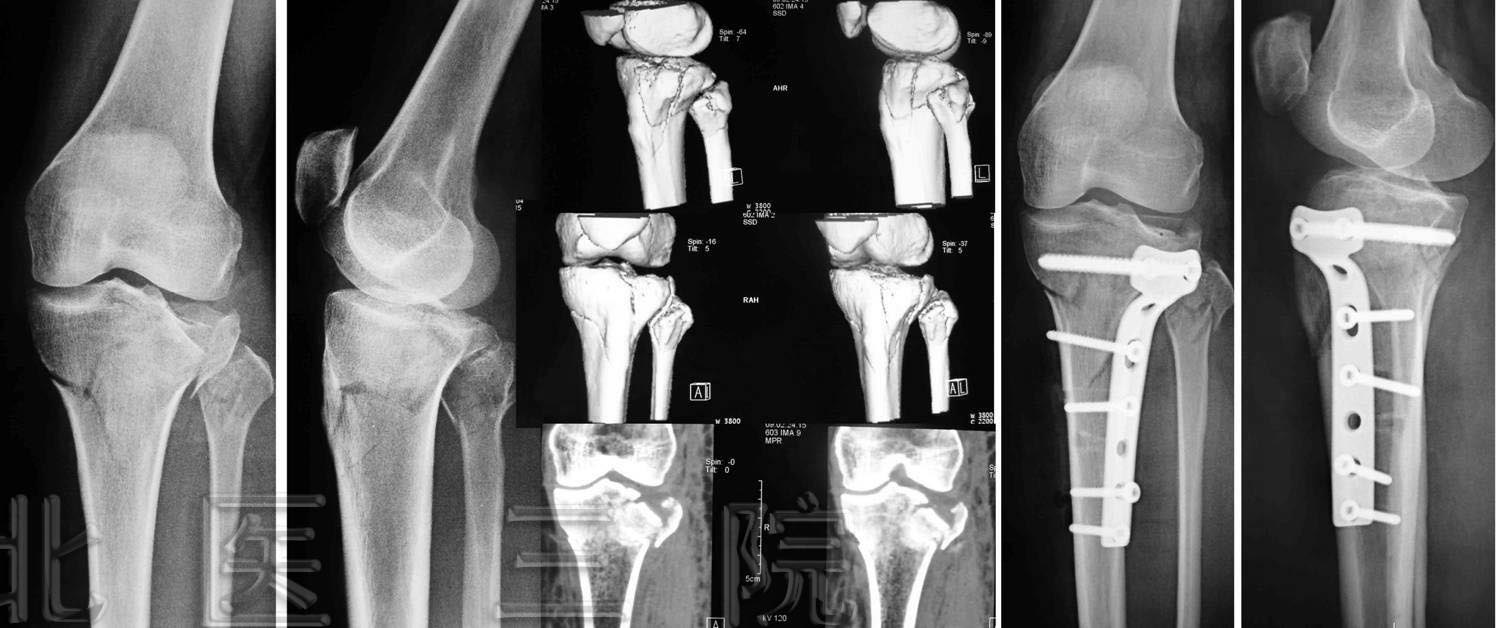

1.女,65岁,肱骨髁间粉碎性骨折,术后肘关节功能大部分恢复

2.前臂双骨折,交锁髓内钉固定

3.桡骨末端掌侧Barton骨折

4.男,35岁,车祸致多发创伤

1)股骨上端骨折

2)胫腓骨下端粉碎性骨折

3)L1、L2骨折

5.女,66岁,外伤致股骨下端骨折,行股骨逆行交锁髓内

钉固定术

6.女,43岁,车祸致胫骨平台骨折

7.男,49岁,胫腓骨骨折,径胫骨髓内钉固定+腓骨钢板固定

8.男,44岁,高处坠落伤致左髋臼、骨盆骨折

9.男,55岁,高处坠落伤致跟骨骨折